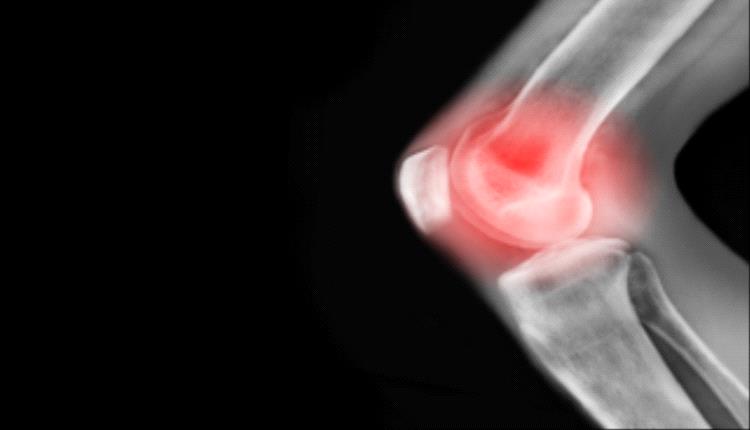

ما أسباب آلام الركبة وكيف يمكن علاجها؟!

يمكن أن يؤثر ألم الركبة المزمن على نشاطك، ويقول الخبراء إن التمارين الأساسية يمكن أن تساعد بشكل كبير في معظم مشاكل الركبة.

وفي معظم الحالات، يتمثل سبب آلام الركبة في الصدمة الناجمة عن إصابة رياضية أو إصابة في العمل.

ويعد تلف الغضروف داخل الركبة وتمزق الأربطة، من الإصابات الشائعة التي تحدث بسبب الصدمة.

وفي حين أن تمزق الغضروف يمكن أن يشفى من تلقاء نفسه، إلا أن الخبراء يحذرون من أن تلف الأربطة قد يتطلب إجراء عملية جراحية.

لكن الخبراء يقولون إن السبب الأكثر شيوعا لألم الركبة يختلف باختلاف العمر. وغالبا ما يكون الألم ناجما عن إصابة أو حركات مفاجئة تضع ضغطا على الركبة، ما يؤدي إلى التواء أو شد أربطة الركبة، أو تمزق الغضروف أو التهاب الأوتار، وفقا للبروفيسور كارين باركر، خبيرة العلاج الطبيعي في جامعة أكسفورد.

ويقول البروفيسور فيليب كوناغان، خبير طب الروماتيزم والعضلات الهيكلية بجامعة ليدز: "قد ينجم ألم الركبة عند البالغين الصغار عن الإصابات الرياضية حيث تتضرر الأوتار المحيطة بالمفصل، أو الغضروف داخل المفصل".

ومع ذلك، بالنسبة للأشخاص الذين تزيد أعمارهم عن 40 عاما، عادة ما يكون ألم الركبة علامة على التهاب المفاصل.

ويقول البروفيسور كوناغان: "هناك العديد من أنواع التهاب المفاصل، لكننا نحاول التمييز بين مشاكل الأوتار والتهاب المفاصل العظمي الشائع جدا، والتهاب المفاصل الالتهابي، مثل التهاب المفاصل الروماتويدي أو النقرس".

وقال: "بشكل عام، تزداد الأمور سوءا كلما وقفت على قدميك خلال اليوم. نحن نعلم أن الأشخاص المصابين بالتهاب المفاصل العظمي غالبا ما يلاحظون الأعراض عند استخدام السلالم". ولكن عندما يتعلق الأمر بالتهاب المفاصل الالتهابي، يعاني الأشخاص من تصلب المفاصل في الصباح لساعات أو نوبات حادة مؤلمة للغاية كما هو الحال في النقرس.

ويقول الخبراء إن العدوى، بما في ذلك السالمونيلا، يمكن أن تسبب أيضا التهابا حادا في المفاصل مع تورم كبير في الركبة.

وعندما يزداد ألم الركبة سوءا مع الحركة دون أي تحسن ملحوظ، ينبغي عليك زيارة الطبيب.

وقال البروفيسور كوناغان: "إذا كنت قد تعرضت لإصابة واضحة في الركبة مع تورم حاد وكبير في الركبة في غضون ساعة، فمن المفيد إجراء فحص لمعرفة ما إذا كنت قد تمزقت أربطة الركبة. وإذا كنت تعاني من تورم كبير في الركبة دون أي صدمة، فقد تحتاج إلى زيارة الطبيب خاصة إذا كانت الركبة ساخنة جدا، أو كنت تعاني من ارتفاع في درجة الحرارة. وإذا كنت تعاني من التهاب المفاصل مثل النقرس أو التهاب المفاصل الروماتويدي وتشعر بزيادة في آلام الركبة أو تورمها، فقد تحتاج إلى تغيير الدواء".

ولكن باركر تقول إنه إذا كانت البداية تدريجية أو غير شديدة التأثير، فيجب على المرضى استخدام الثلج وإراحة المفصل لمواجهة التورم واستخدام مسكنات الألم التي لا تستلزم وصفة طبية، مثل الباراسيتامول، للتحكم في الألم.

وقالت: "الجراحة هي العلاج الأخير لالتهاب مفاصل الركبة، وينبغي النظر فيها فقط في حالة التهاب المفاصل الحاد عندما تفشل التدابير الأخرى في المساعدة مثل إدارة فقدان الوزن والعلاج الطبيعي ومسكنات الألم".